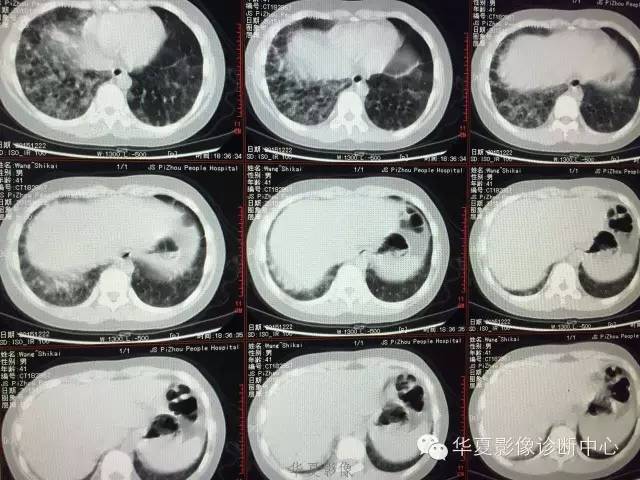

支原体肺炎1例CT影像表现